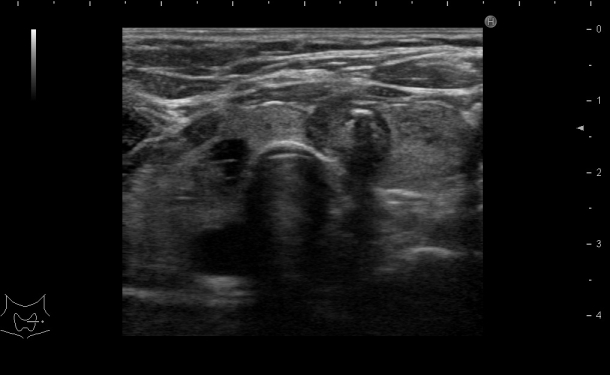

甲状腺超音波検査

甲状腺の大きさや形態、実質に変化がないかを観察します。

内部に腫瘤があれば、超音波上での良悪性の鑑別をします。